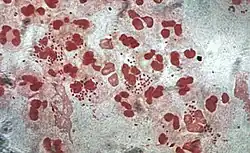

Neutrophils are normally found in the bloodstream and are the most abundant type of phagocyte, constituting 50% to 60% of the total circulating white blood cells.[77] One litre of human blood contains about five billion neutrophils,[3] which are about 10 micrometers in diameter[78] and live for only about five days.[39] Once they have received the appropriate signals, it takes them about thirty minutes to leave the blood and reach the site of an infection.[68] They are ferocious eaters and rapidly engulf invaders coated with antibodies and complement, and damaged cells or cellular debris. Neutrophils do not return to the blood; they turn into pus cells and die.[68] Mature neutrophils are smaller than monocytes and have a segmented nucleus with several sections; each section is connected by chromatin filaments—neutrophils can have 2–5 segments. Neutrophils do not normally exit the bone marrow until maturity but during an infection neutrophil precursors called metamyelocytes, myelocytes and promyelocytes are released.[79]

The intra-cellular granules of the human neutrophil have long been recognized for their protein-destroying and bactericidal properties.[80] Neutrophils can secrete products that stimulate monocytes and macrophages. Neutrophil secretions increase phagocytosis and the formation of reactive oxygen compounds involved in intracellular killing.[81] Secretions from the primary granules of neutrophils stimulate the phagocytosis of IgG-antibody-coated bacteria.[82] When encountering bacteria, fungi or activated platelets they produce web-like chromatin structures known as neutrophil extracellular traps (NETs). Composed mainly of DNA, NETs cause death by a process called netosis – after the pathogens are trapped in NETs they are killed by oxidative and non-oxidative mechanisms.[83]